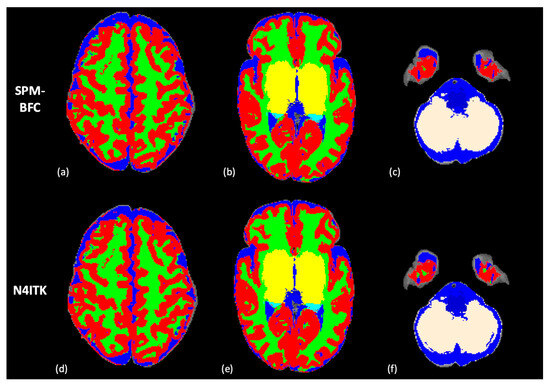

3.1. Assessment of Intensity Variability and Segmentation Performance

3.2.1. Comparison Between Bias Field Correction Methods